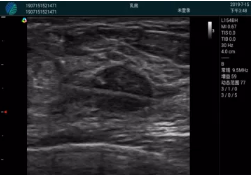

腺體內(nèi)部清晰顯示一低回聲塊影,形態(tài)不規(guī)則,邊界模糊,邊緣呈毛刺狀,內(nèi)部見砂礫樣鈣化

M20引導(dǎo)下穿刺活檢術(shù)

M20引導(dǎo)下平面內(nèi)穿刺取出的腫塊組織